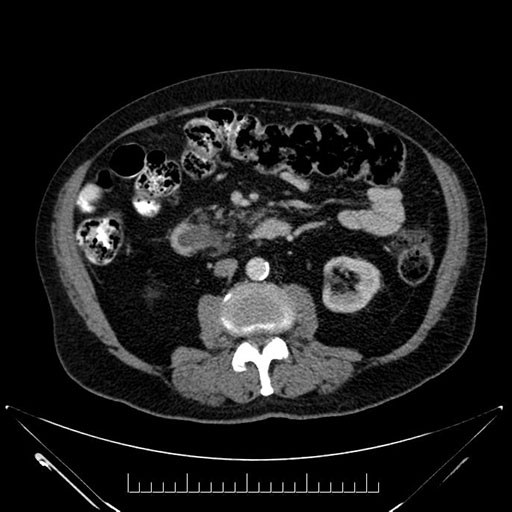

Imaging Analysis

Look through the patient's CT scan to identify any areas of concern for the necessary procedure.

Based on your CT findings, which issue(s) would give reason for "planned slowing down moment(s)" in this case?

Considering a standard Whipple procedure, what step(s) of the operation would you do differently in this case?